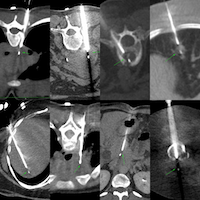

55-yrs old with an incidentally discovered multiloculated cystic lesion in the retroperitoneum was referred for a biopsy.

Milky white fluid was aspirated using a left parapsoas approach.

The video discusses the case, the diagnosis based on the appearance of the aspirate and two other similar cases.

Region: Retroperitoneum

Findings: Retroperitoneal multiloculated cyst

No of cores: Tried, but no solid cores, 35 cc of milky white fluid

Position & Approach: Prone, blunt-tip

Diagnosis: Retroperitoneal macrocystic lymphatic malformation